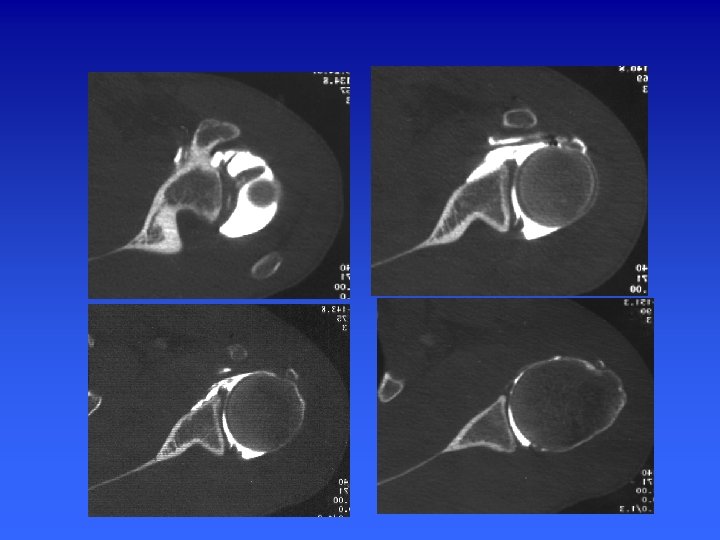

ARTHROSCANNER EPAULE n Positionnement : épaule en position neutre n Topogramme : art acromio-clav - pointe omoplate n Acquisition : hélicoïdale millimétrique de l’articulation acromio-clav jusqu’au rebord inf de la glène n Pitch de 1 à 1, 5 et un incrément de reconstruction de 0, 5 mm. W= 2500/600

ARTHROSCANNER EPAULE n Reformatage Axial perpendiculaire à la glène n Para-saggitales dans le plan d’obliquité de la glène n Para-frontal, perpendiculaire au plan de la glène n

Représentation schématique de la coupe d’arthroscanner passant par le pôle supérieur de la tête humérale

Acquisition en axial Reconstruction 2 D Para sagittale dans le plan // à la glène Coronale ou frontale Plan perpend. à la glène Sagittale